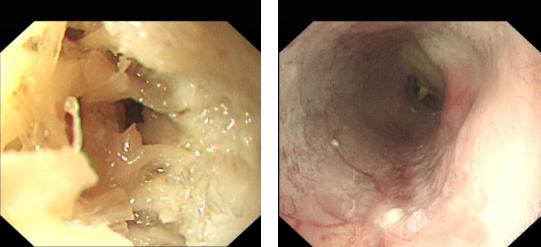

梁小波主任帶領(lǐng)消化內(nèi)科團(tuán)隊(duì)對(duì)魏婆婆完善相關(guān)檢查、給予營(yíng)養(yǎng)支持、胃鏡前評(píng)估等系列準(zhǔn)備工作后,在魏婆婆入院第四天,李學(xué)志副主任醫(yī)師順利為老人完成胃鏡檢查,同時(shí)進(jìn)行了治療。

魏婆婆在經(jīng)胃鏡治療后禁食一天,第二天就可以進(jìn)食流質(zhì)的食物了。目前魏婆婆身體恢復(fù)良好。這個(gè)案例也開(kāi)創(chuàng)了茂名地區(qū)年紀(jì)最大患者內(nèi)鏡下治療的記錄。